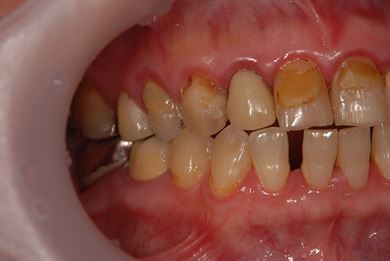

| 性別/年齢 | 女性 / 51歳 | ||||||||||||||||||||||||||||||||

| 主訴 | 前の歯の治療後の変色が気になる。詰め物がとれた箇所あり。痛みあり。 | ||||||||||||||||||||||||||||||||

| 治療方針 | セラミック治療にて、審美的回復を行う。 | ||||||||||||||||||||||||||||||||

| 治療内容 | オールセラミッククラウン7本(オールセラミック用土台1本)、ハイブリッドセラミッククラウン10本(ハイブリッドセラミック用土台9本)、ハイブリッドセラミックインレー1本 | ||||||||||||||||||||||||||||||||